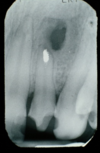

what is shown on this picture?

periacpical granuloma